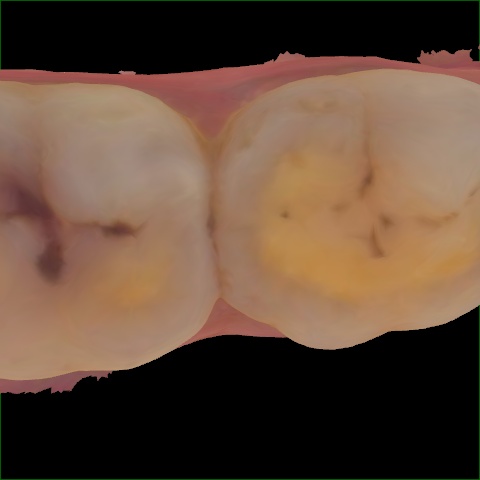

Image 199 / 400

NHD25467

Annotated as "Good"

Original Image Rendering Image